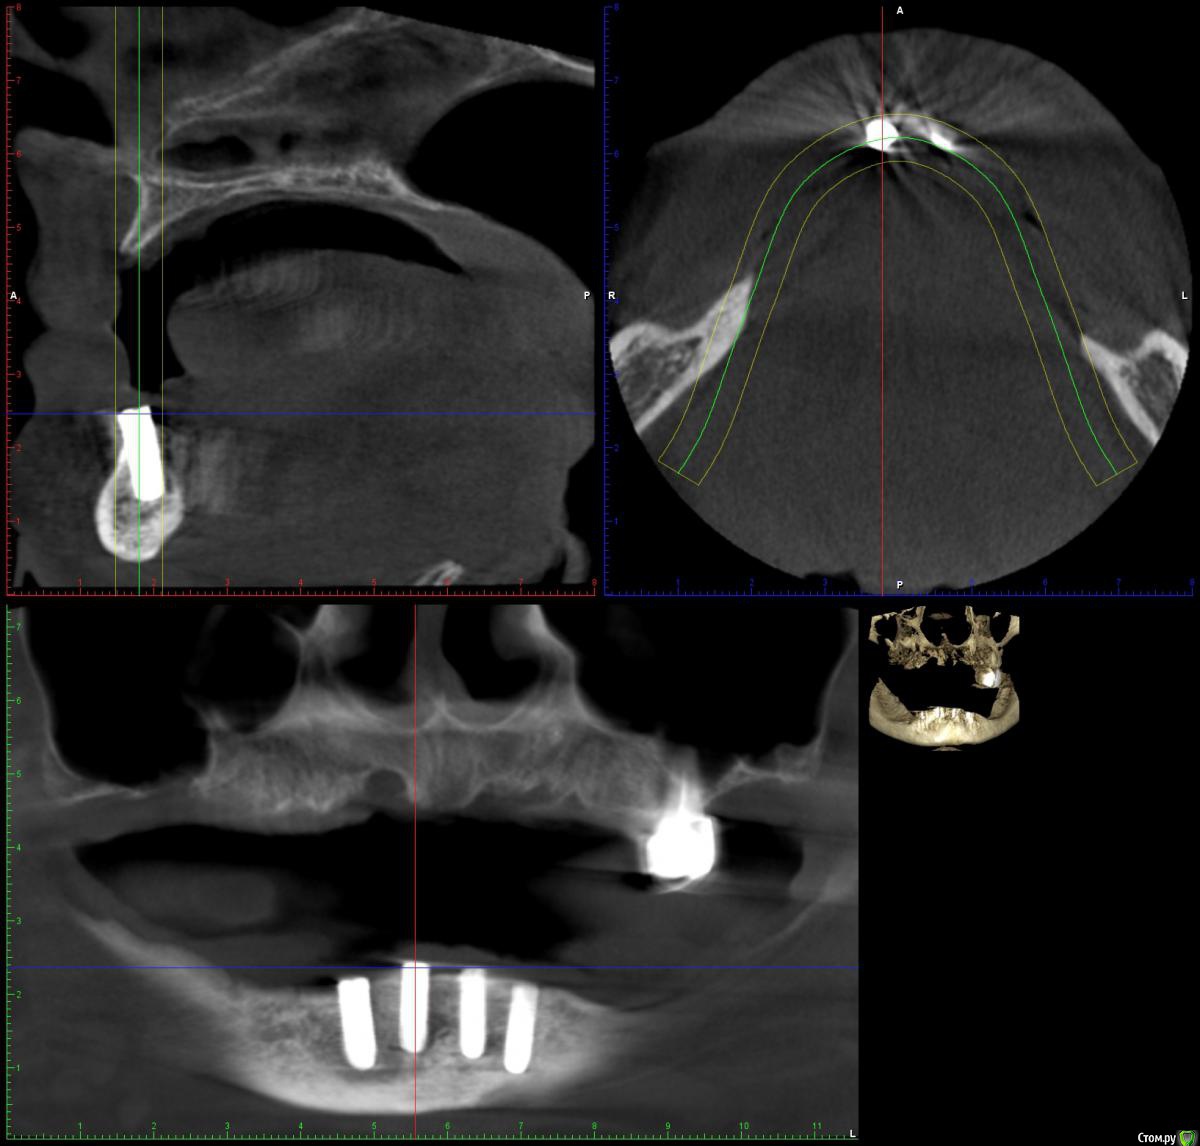

Артур К. Опубликовано 5 июня, 2016 Поделиться Опубликовано 5 июня, 2016 Добрый день! Пациенту (женщина, 50 лет) три месяца назад установили 4 импланта (BEGO Semados, если это имеет значение) в нижнюю челюсть под установку протеза. Один из имплантов (второй справа) до сегодняшнего дня причиняет дискомфорт, а при давлении сверху (просто небольшое давление пальцем на десну) боль. Не острая, но вынуждает всё это время исключать правую часть челюсти из жевания (на нижней челюсти съемный протез). В течение примерно месяца после операции в районе этого импланта был небольшой, но заметный отёк. При этом никаких признаков воспаления нет, врач говорит, что всё нормально и на ближайшее время назначает установку формирователей десны. На вопрос о причине боли разводит руками. Подскажите, пожалуйста, насколько это нормально, в чём может быть причина боли? Есть ли смысл не торопиться с установкой формирователей десны и обратиться к другому специалисту за консультацией? Врачу доверяем, но по всем отзывам имплант не должен причинять никакой боли (так и есть с тремя остальными), а установка протеза при сохранении боли вообще становится бессмысленной. Ссылка на комментарий